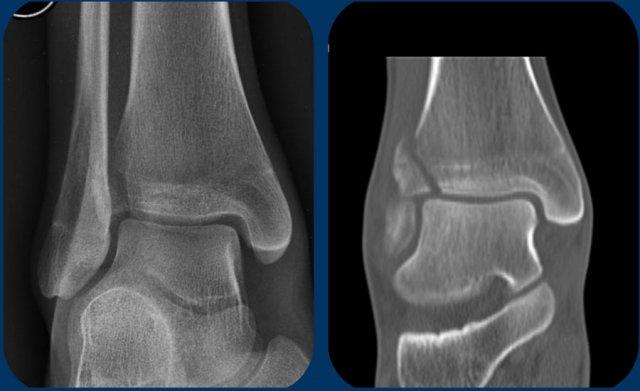

Đôi khi chúng ta may mắn vì đường gãy xương mác có thể nhìn thấy trên X-quang cổ chân.

Khi đó chúng ta biết mình đang đối mặt với gãy xương Weber C giai đoạn 3 không ổn định.

Trong trường hợp này, có sự giãn rộng khoang sáng phía trong (medial clear space) giữa mắt cá trong và xương sên, cho thấy đứt dây chằng bên trong (giai đoạn 1).

Chúng ta phải giả định rằng cũng có đứt khớp chày mác xa phía trước (giai đoạn 2).

Ngoài ra cũng có thể có tổn thương giai đoạn 4 ở khớp chày mác xa phía sau.

Tuy nhiên, trong nhiều trường hợp, đường gãy xương mác nằm ở vị trí cao hơn và chúng ta cần chụp thêm X-quang để tìm đường gãy.

Nhiệm vụ của chúng ta với tư cách là bác sĩ chẩn đoán hình ảnh là tìm kiếm các dấu hiệu gợi ý trên X-quang cổ chân để dẫn đến các đường gãy xương mác cao này, và thuật toán sẽ hỗ trợ chúng ta trong việc đó.